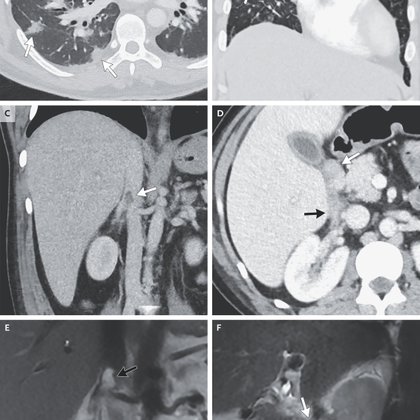

nejm.org

A 36-year-old man was admitted because of fever, hypoxemia, and bacteremia. Imaging revealed pulmonary opacities, thickening of the duodenal wall, and a thrombus in the right renal vein. A diagnosi...